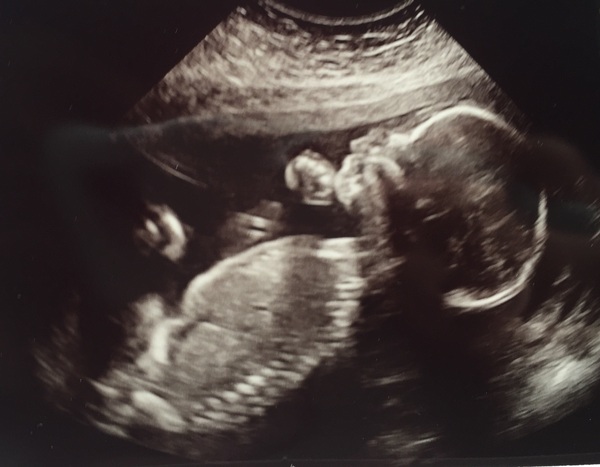

This is our littlest boy Grin. Wasn't going to get a pic, but I'm glad we did.